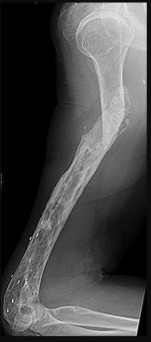

This patient has a dedifferentiated liposarcoma within a preexisting atypical lipomatous tumor. The imaging demonstrates a large fatty mass with increased internal septations proximally (the atypical lipomatous tumor) and a solid enhancing mass distally (the dedifferentiated portion). A biopsy reveals a high-grade liposarcoma. The other diagnostic responses do not reflect sarcomatous transformation of the lesion.

Surgical treatment of a high-grade sarcoma involves wide surgical resection. Radiation decreases local recurrence but does not clearly influence overall survival. The role of chemotherapy in high-grade soft-tissue sarcomas remains investigational; there is a modest (8%-15%) associated improvement in overall survival.

Intramuscular lipomas and atypical lipomatous tumors are treated with marginal resection alone. Radiation therapy for soft-tissue sarcomas may be given before or after surgery. When administered before surgery, patients have a higher wound complication rate but better long-term function attributable to lower rates of lymphedema, fibrosis, and contractures.